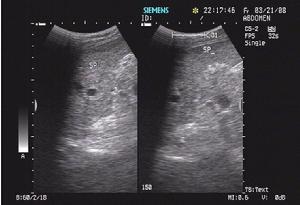

2.腹部超聲檢查 當脾臟損傷時可顯示脾輪廓不整齊,影像中斷,疑有包膜下血腫,並可見脾臟進行性腫大和雙重輪廓影像,同時可顯示腹腔內100ml 以上的積液。脾包膜斷裂時,可見脾臟表面欠光滑整齊,連續性中斷,可探及條索狀暗帶,脾實質回聲尚均勻,脾周及左右髂窩內可探及不等量的液性暗區。當包膜、脾實質同時斷裂時,可見脾臟包膜斷裂,脾實質內可探及一處或多處不規則低回聲區,脾周、肝前、肝腎之間、左右髂窩可探及大量液性暗區。遲發性脾臟破裂時,需多次超聲檢查才能發現實質破裂。